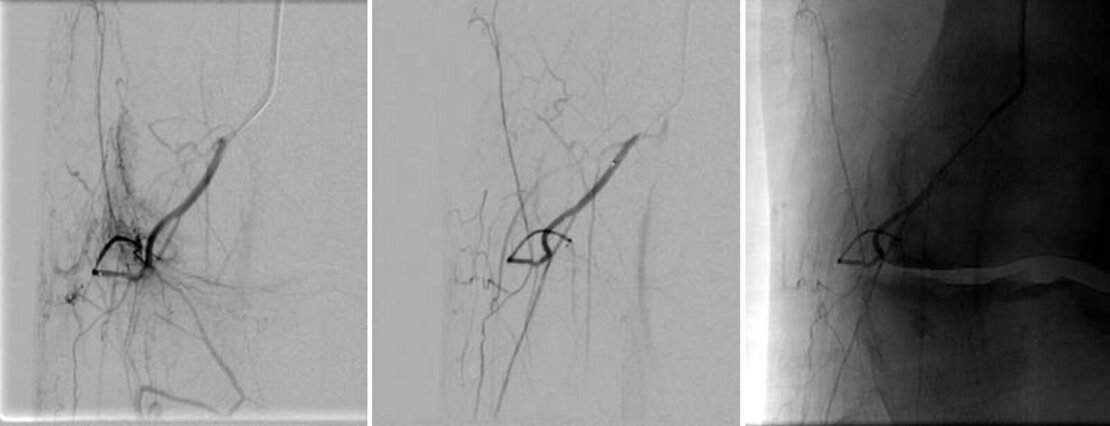

Behandlungsbeispiel aus unserer Klinik

Nach einer lokalen Betäubung in der Leiste wird ein kleiner Katheter in die Hauptschlagader des Beins eingeführt und bis zu den Kniegelenkversorgenden Gefäßen vorgeschoben. Die kleinen Gefäße, welche das Kniegelenk versorgen, werden gezielt mittels eines Mikrokatheters mit einem Durchmesser von 0,51 mm untersucht. Wenn das Gewebe in einer bestimmten Region vermehrt Kontrastmittel aufnimmt, deutet das auf eine Entzündungsreaktion hin. In diesem Fall wird in die betreffenden Gefäße ein Medikament gespritzt, welches diese zeitweise verschließt. Dies bezeichnet man auch als Embolisation.